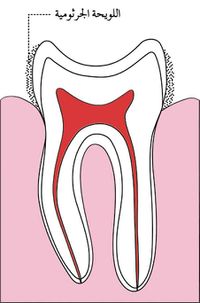

اللويجة الجرثومية

تتوضع على سطوح الأسنان طبقة عضوية رقيقة تدعى اللويحة الجرثومية bacterial plaque تتألف من طبقات كثيفة ومتراصة من الجراثيم ومنتجاتها والخلايا والبقايا الطعامية، وهي ذات طبيعة سكرية بروتينية لا تنحل باللعاب ولا تزول بغسلها بالماء بل تحتاج إلى فرشاة الأسنان لإزالتها.

ووتكون اللويجة الجرثومية على مرحلتين:

- المرحلة الأولى: وتبدأ بعد 30 دقيقة من تنظيف الأسنان إذ يفرز اللعاب مواد سكرية بروتينية تلتصق بسطح السن وتكون غشاء رقيقاً غير جرثومي يدعى الجليدة أو القشيرة pellicle وهو غير قابل للانحلال ولا يرى بالعين المجردة.

- المرحلة الثانية: تأخذ الجراثيم، في غضون ساعة، وخاصة المكورات العقدية الإيجابية الغرام gram positive Streptococcus منها بالتوضع على الجليدة ثم تأخذ أنواع أخرى من الجراثيم بالتراكم تدريجياً في3 - 8 ساعات. وتضم العقديات: العقديات الدموية S.sanguis والعقديات الطافرة S.mutans التي يزداد وجودها في اللويحة الجرثومية لدى تناول السكريات (السكاروز) باستمرار عن طريق الغذاء، ويعزى للعقديات الطافرة قيامها بدور أساسي في بدء حدوث التسوس إذ تقوم باستقلاب السكاروز مكوّنةً حموضاً ومواد لاصقة من نوع متعدد السكريد كالدكستران. وتوجد أيضاً العقديات اللعابية S.salivarious والشعيات اللزجة viscous Actinomyces.

وتأخذ أنواع أخرى من الجراثيم في 24 ساعة من بدء تكوّن اللويحة بالتوضع عليها مثل العقديات اللاهوائية السلبية الغرام والعصيات اللبنية Lactobacillus، وفي 3-7 أيام التالية تتراكم أحياء مجهرية أخرى مثل الحليزونيات Spirilla والعصيات المغزلية Fusiform Bacilli والملتويات Spirochetaceae والألياف وتصبح اللويحة في حالة نضج ويكون لها تأثير ضار على اللثة أيضاً إضافة إلى دورها في إحداث التسوس.